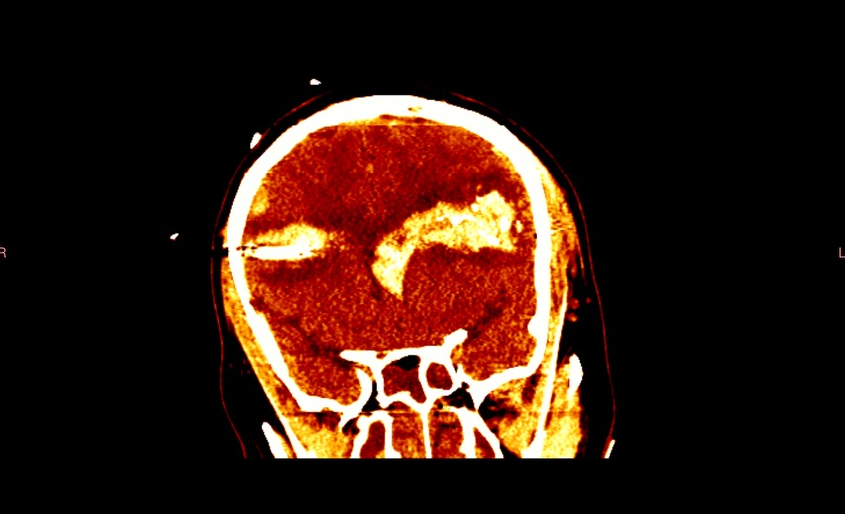

Hans arrived unresponsive at the hospital. A CT scan revealed a bullet in his brain.

One of the most unique parts of Hans' recovery is that he now lives with bullet fragments in his brain. Doctors decided that it was too risky to operate to remove what's left.